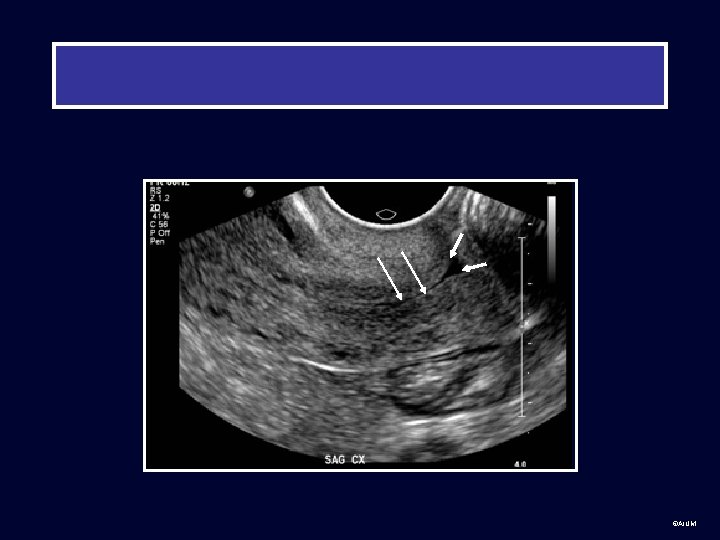

©AIUM

©AIUM